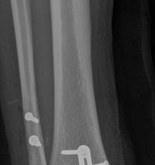

Complications and Management

Despite meticulous surgical technique, the management of partial articular fractures carries a significant risk of complications. Early recognition and aggressive management are paramount to preserving limb function.

Complication Incidence Etiology/Risk Factors Management and Salvage Strategies

Deep Surgical Site Infection 2% - 8% Poor soft tissue envelope, early incision, diabetes, smoking Aggressive serial debridement, hardware retention (if stable) vs removal (if loose), culture-directed IV antibiotics, soft tissue coverage (flaps).

Secondary Articular Subsidence 5% - 15% Inadequate bone grafting, premature weight-bearing, severe osteoporosis Revision open reduction and internal fixation (ORIF) with structural grafting. In elderly patients with severe destruction, conversion to total joint arthroplasty may be indicated.

Post-Traumatic Osteoarthritis 10% - 30% Initial cartilage impaction damage, residual articular step-off > 2mm, malalignment Conservative management initially (NSAIDs, injections). Definitive management via corrective osteotomy (if joint preserved) or arthrodesis/arthroplasty.

Joint Stiffness / Arthrofibrosis 10% - 20% Prolonged immobilization, excessive surgical trauma, prominent hardware Aggressive physical therapy. If refractory, hardware removal and arthroscopic or open lysis of adhesions / manipulation under anesthesia (MUA).

Hardware Failure / Loss of Fixation < 5% Failure to achieve buttress effect, unrecognized diaphyseal extension, non-compliance Revision ORIF with robust fixed-angle constructs, spanning plates, and augmentation with bone graft to address non-union or delayed union.